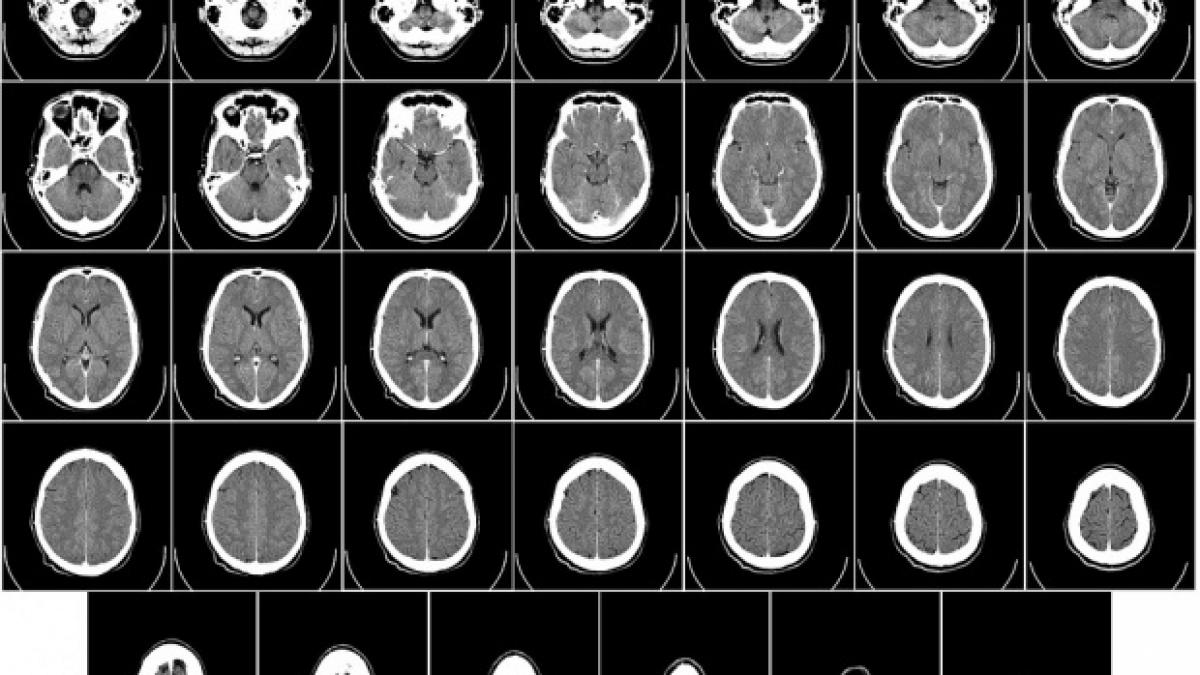

Premieră mondială: Un vierme viu fost găsit în creierul unei femei, în Australia | "A fost o descoperire unică în carieră"29 Aug